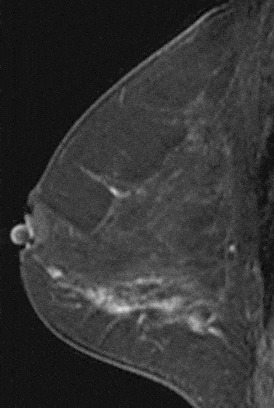

Figure 7. Spiculated mass. Pathology – Invasive lobular cancer.

Certain morphologic characteristics are very suggestive of malignancy. Findings that are highly predictive of malignant disease include spiculated margins (positive predictive value (PPV) = 76–88%) and rim enhancement (PPV = 79–92%) [6,14].

The strongest correlations that Nunes et al. [6,14] found between lesion appearance and pathologic findings were: smooth mass and fibrocystic change, lobulated mass with non-enhancing internal septations and fibroadenoma, enhancing irregular or spiculated mass and invasive ductal carcinoma, spiculated mass and invasive tubular carcinoma or radial scar, enhancing lobulated mass and medullary or colloid carcinoma, ductal enhancement and DCIS, and regional enhancement and DCIS.

Liberman et al. [15] found that features with the highest PPV for masses were spiculated margin, rim enhancement and irregular shape, and for non-masses segmental or clumped linear or ductal enhancement.